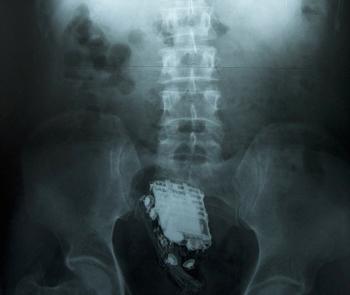

한 죄수가 자신의 항문 속에 휴대전화를 넣어 감옥으로 돌아오다 갑자기 울린 벨소리 때문에 발각된 황당한 일이 벌어졌다.

지난 6일(이하 현지시간) 스리랑카 콜롬보 외곽 웰리카다 교도소에서 10년형을 선고받고 복역중인 한 죄수(58)가 기상천외한 방법으로 휴대전화 반입을 시도했다.

그의 방법은 바로 항문 속으로 휴대전화를 밀어넣는 것. 극한의 고통을 참고 직장까지 휴대전화를 밀어넣은 그는 간수들의 눈을 피하는데 성공했으나 귀를 피하지는 못했다.

간수 옆을 무사히 지나치는 순간 갑자기 전화 벨소리가 울린 것. 제대로 타이밍 맞춘 벨소리 탓에 그는 결국 죄목 하나를 더 추가하게 됐다.

발각 직후 죄수는 인근 병원으로 후송됐으며 의사들은 진땀을 흘리며 무사히 직장 속에서 냄새나는 휴대전화를 빼내는데 성공했다.